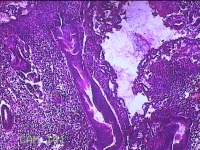

子宫腔赘生物(大)

性别

女

年龄

38岁

临床诊断

子宫内膜息肉;子宫异常出血

一般病史

月经量多数年,发现宫腔占位1个月。

标本名称

大体所见

灰白暗红色不规则肿物2.7x1.8x0.8cm一堆,切开肿物呈实性,切面灰白暗红色,质软。

有那么点像子宫内膜息肉,片子这个效果,辩认起来非常困难。